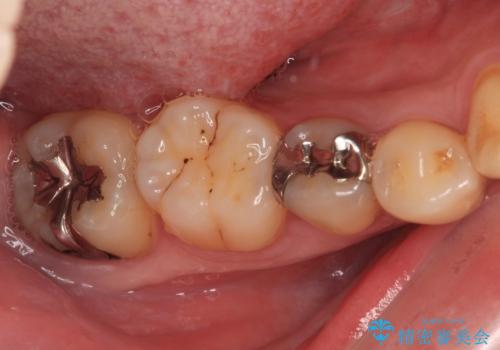

- 銀歯やむし歯でものが挟まるところが気になるとのことで来院された患者様です。

その他は銀歯のインレー(部分的な詰め物)が装着されており、それらはむし歯を除去した後にセラミックインレーにて修復治療を行い、左下と根管治療を行う左上の奥歯はオールセラミッククラウンにて補綴治療を行うこととしました。

根管治療の途中で、矯正治療の後戻りが気になるとのことで、下顎前歯の叢生を改善するためにマウスピース矯正を並行して行いました。